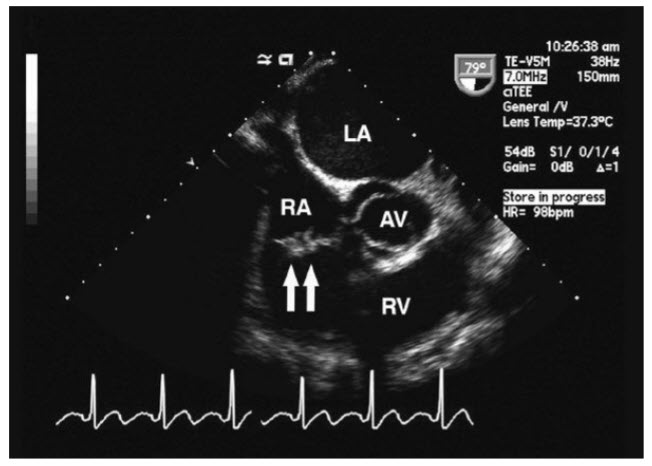

Intravenous (IV) drug abuser. Right-sided endocarditis is less common than left-sided endocarditis. The TEE image (Fig. below) shown demonstrates a patient with a vegetation on the tricuspid valve, and the organism identified by culture is Pseudomonas. This is associated with IV drug use with contamination at the time of injection. Although the other clinical situations listed are at increased risk for endocarditis (typically left sided), Pseudomonas would be a very unusual pathogen in those situations.